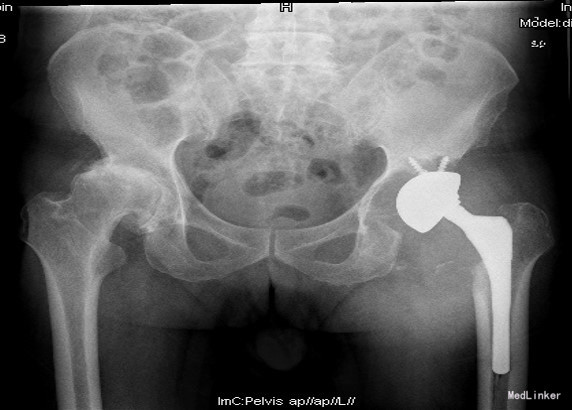

查体:左腹股沟区可见瘢痕及色素沉着,左腹股沟区可触及质硬包块,触之胀痛,局部皮温正常,左下肢内侧皮肤麻木。左髋外展10°,内收10°,屈曲80°,伸0°,内旋0°,外旋5°,右髋外展20°,内收15°,屈90°,伸0°,内旋10°,外旋10°,双髋内、外旋活动诱发疼痛;双下肢基本等长,双侧4字试验(+)。 辅助检查:双髋内、外旋活动诱发疼痛;双下肢基本等长,双侧4字试验(+)。X线片:左髋THA后假体向上移位,右侧股骨形态失常,关节间隙变窄

诊断:1.左侧THA术后假体松动、聚乙烯内衬磨损、炎性假瘤形成 2.左侧THA术后髋臼及股骨近端骨溶解 3.左侧THA术后髋臼及股骨近端骨缺损(髋臼AAOS III型 股骨Paprosky II型) 4.右髋重度骨关节炎 5.高血压 (2期 高危) 治疗:完善检查,调整患者全身条件后在全麻下行左侧全髋关节假体取出+炎性假瘤切除+异体骨植骨+髋臼重建+人工全髋关节翻修术,术中发现:左髋关节囊后外侧炎性假瘤形成,与关节腔相通,内有大量咖啡色混浊液体,髋臼及股骨近端骨溶解导致骨缺损,以髋臼前壁及下壁和股骨近端严重,小转子消失,关节腔周围大量炎性坏死组织。髋臼假体松动。术中安放左侧Zimmer64mmCage,并用8枚不同长度螺钉固定可靠,Cage内放骨水泥后安放外径59mm,内径28mm聚乙烯内衬并调整前倾及外展角度合适,股骨侧安放12#加长股骨柄,28mm直径、+1.5颈长陶瓷股骨头。